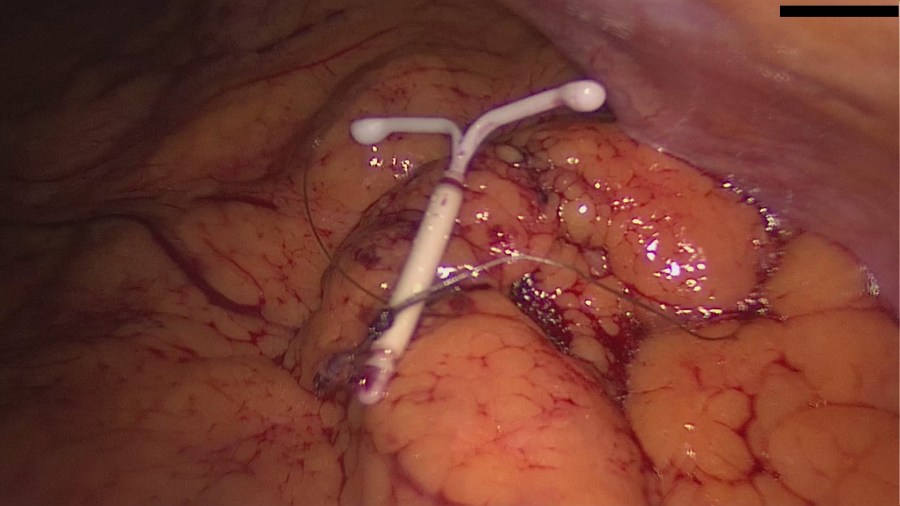

A 24-year old G0 presented with acute lower abdominal pain with sudden onset three days ago, accompanied by nausea and vomiting. Just as the pain seemed to subside, the patient developed fever, which eventually led her to the clinic. The laboratory results revealed leucocytosis and increased CRP. The patient also mentioned periodic attacks of lower abdominal pain throughout the previous year, which on the contrary subsided a lot quicker.

Fallopian tube torsion is a rare condition caused mainly by the presence of enlarged paratubal cysts. If the treatment is delayed, a torsion may lead to necrosis, similar to the consequences of an adnexal torsion. You can read more about adnexal torsion, here.